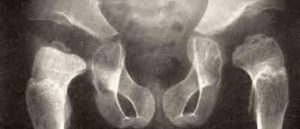

Рентгенографическое исследование тазобедренных суставов у детей, у которых заподозрена дисплазия Майера, позволило обнаружить более позднее по сравнению с нормой появление ядер оссификации. Наблюдается уменьшение в размерах либо недоразвитие хрящевой части эпифиза бедра.

Ядра окостенения появляются с запозданием, может появиться одно ядро и несколько сразу. В ряде случаев подобное приводит к ошибкам в диагностике, такое состояние расценивается, как очаги асептического некроза головки бедренной кости.

В конце прогрессирования дисплазии Майера возможно обнаружить на рентгеновском снимке сформировавшийся эпифиз бедренной кости с невыраженным уменьшением его размеров. Структура костной ткани и хрящевого покрытия при этом не имеет отклонений.

Рентгенограмма и ультразвуковое обследование отображают несовпадение центральной точки головки бедренной кости с центральной точкой в вертлужной впадине.